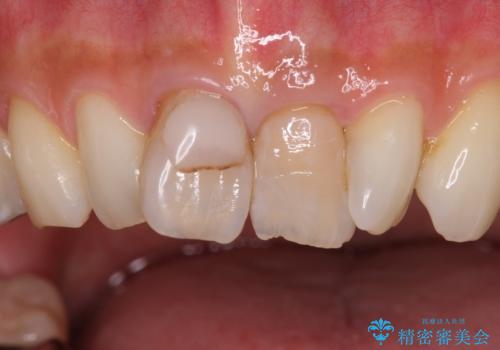

- 前歯の変色とガタつきがきになるとのことで来院されました。

矯正治療の希望はなかったため、セラミッククラウンで被せて治療していくことになりました。

元々根管治療がされていたにも関わらず被せ物が作られておらず、このままではどんどん変色が進んでいってしまう状態でした。

歯をある程度削ることにはなりますが、被せ物にすることで歯の変色を隠し短期間でキレイな口元に仕上げることができました。